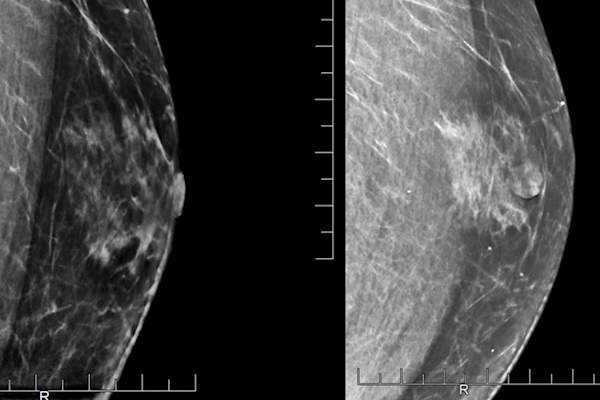

BREM博士说,男性与BRCA2基因突变应该得到尽可能多的女性做筛查。这意味着定期乳房X线照片。虽然有些妇女与BRCA突变提供了一个预防(防止)乳房切除术,Nangia博士,这不是通常提供给男性说。